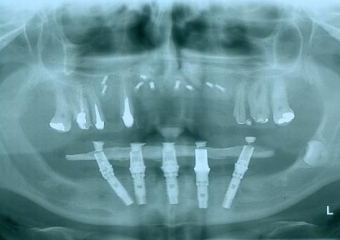

Raio - x com implantes inferiores em Junho de 2014  - Clínica Cliniface

Raio - x com implantes inferiores em Junho de 2014